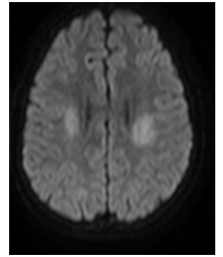

A CT (Computerized Tomography) scan of the skull was requested and did not show any signs of intracranial hemorrhage. Subsequently, magnetic resonance imaging (MRI) of the brain was performed, evidencing two focal areas of high signal in DWI in bilateral centrum semiovale (Figures 1‒5). Considering that the treatment wasn`t finished and still consisted in high and continuous doses of MTX, aminophylline was introduced in order to prevent/reverse the effects of the subacute ischemic event due to the medication.

Figure 1 Focal and symmetrical regions of restricted diffusion on DWI on centrum semiovale.

Figure 4 Focal and symmetrical regions of restricted diffusion on DWI on centrum semiovale.